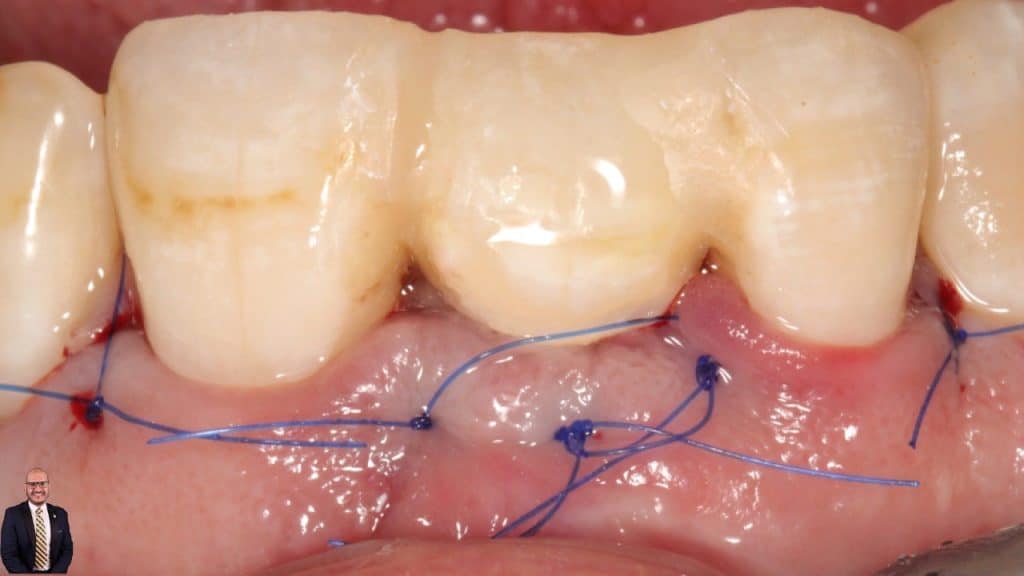

Type III socket patient, High risk esthetic case presented with hopeless #11, managed by staged approach to optimize patient’s expectations.